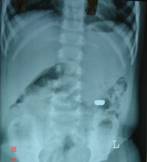

After the baby is born, small bowel atresia is usually diagnosed when there are signs of an obstruction, such as vomiting, green bile and a swollen abdomen. An x-ray scan may show a blockage. Occasionally, doctors may suggest using a contrast scan and/or enema instead or as well as an x-ray.

Contrast scans and enemas use a thick, white liquid called barium or a clear liquid (contrast), both of which show up well on x-rays. The contrast cannot pass through the atresia suggests that atresia can be a cause.